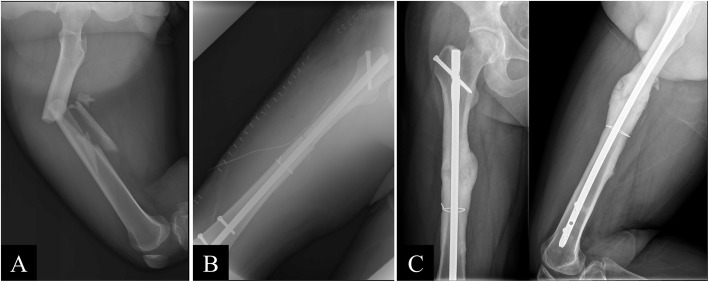

Fig. 2 .

(A) Preoperative, (B) postoperative, and (C) 14-month postoperative images of a 24-year-old man with a comminuted fracture of the right femur from a traffic accident. Reduction was successfully achieved using open cerclage wiring, and the fracture healed 14 months after the surgery